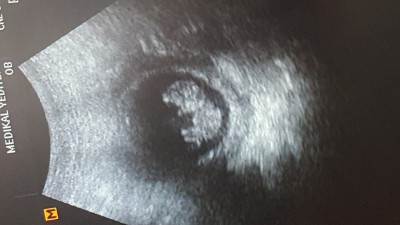

Iyi aksamalar sevgili anneler 10 haftalık hamileyim ve doktor muaynesinde sevgili doktorum kese ve kalp atış hızına göre cinsiyet tahmin etti bu durumu yaşamış ve doğrulanmış olan annelerimiz varmi?

Gebelik haftası 10

Yüzde 80 kız bence canım Allahtan hayırlısı olsun tabi

3 kızdan sonra erkek ihtimaliniz de çok yüksek fakat kese duruş şeklini ben kıza benzettim Allah gönlünüze göre versin tabi inşallah, bir de ovulasyon günü erkek bebek ihtimali çok artıyor bir de diyet listeleri var tuzlu ve protein ağırlıklı dediğim gibi bu benim düşüncem ama gönlünüzdeki olsun isterim sağlıcakla